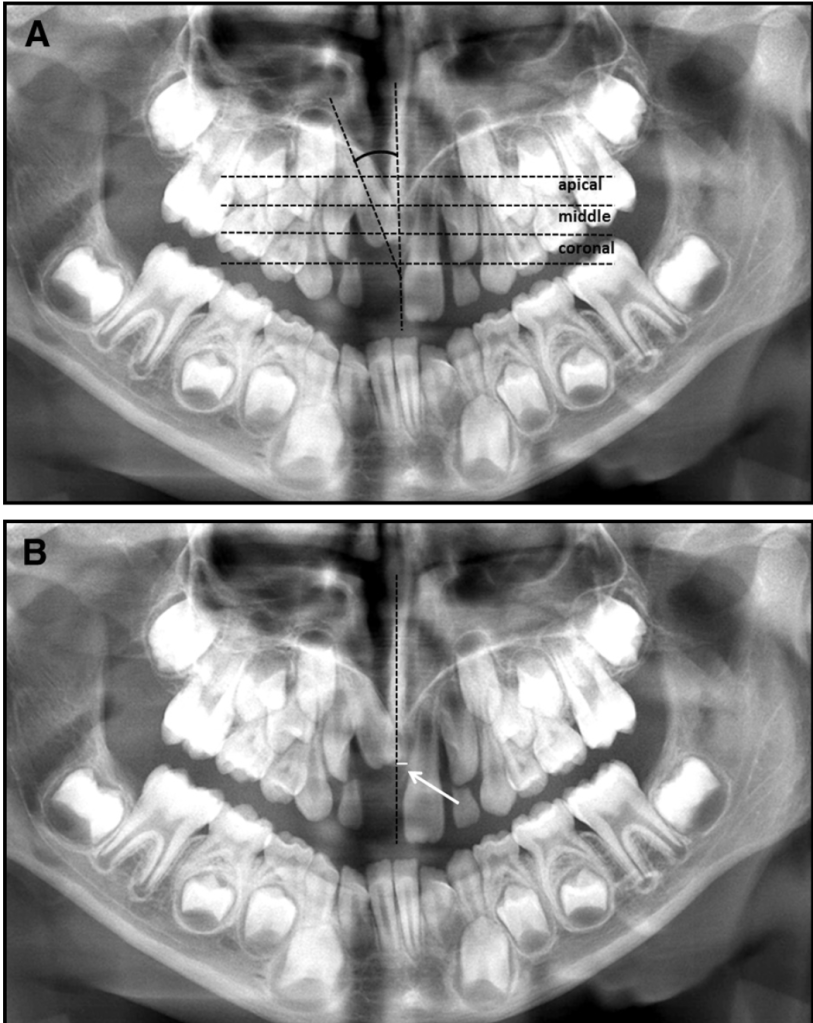

That detour results in the tooth bending its root like it’s doing a deep downward dog. š§āāļø This abnormal bend or curve in the root or crown is what we call dilaceration.

š¬ Dr. Walia et al. (2016) explain that trauma gets transmitted via the primary incisorās apex to the Hertwigās Epithelial Root Sheath of the developing permanent tooth. This damages its root-forming potential and leads toāyou guessed itāroot yoga (aka dilaceration). š§āāļø

𤯠But What If the Tooth is Dilacerated?

Root bends = eruption confusion = š§© difficult alignment.

2ļøā£ Initial Height

- Higher up the tooth, longer the rescue mission (especially T2 stage). ā³